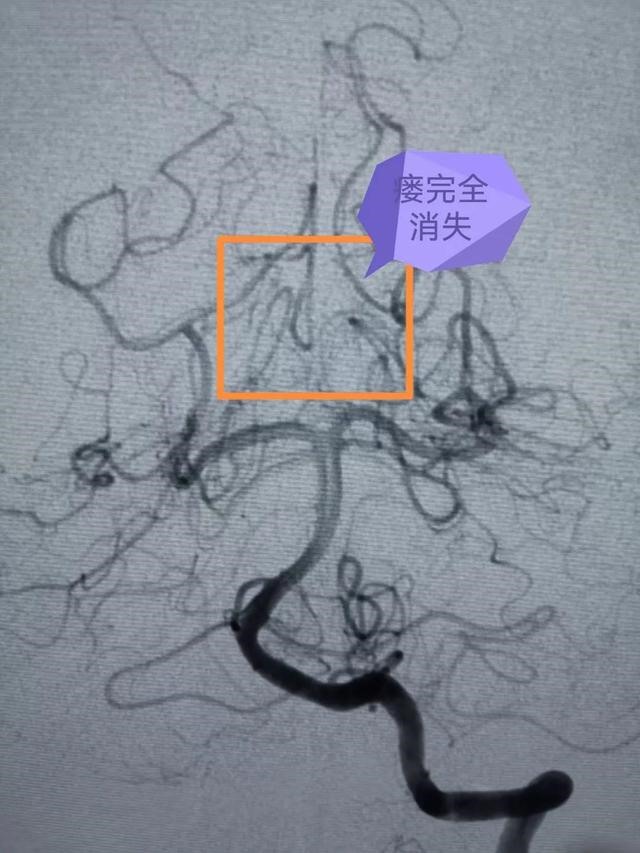

专家团队在大梅的大腿根部股动脉穿入笔芯粗细的导管,然后在脑血管造影机的X线引导下,将一米多长的细若发丝的微导管通过血管小心翼翼送至脑血管畸形部位,由于血管畸形位于脑深部,供血动脉迂曲细长,角度刁钻,手术困难极大,但是专家团队小心仔细,锲而不舍,经过5个多小时的紧张手术,最终将脑血管畸形完全栓塞。手术后,大梅的脑部畸形团块消失,恢复良好。

潘剑威主任医师介绍,脑血管介入是目前医学领域更先进的脑血管疾病诊断治疗之一,创伤小、恢复快,随着设备、材料、技术的不断进步,越来越多的脑血管疾病可以通过脑血管介入得到诊治。但同时,脑血管介入对手术医生的技术、心力、脑力和体力都有极高的要求。